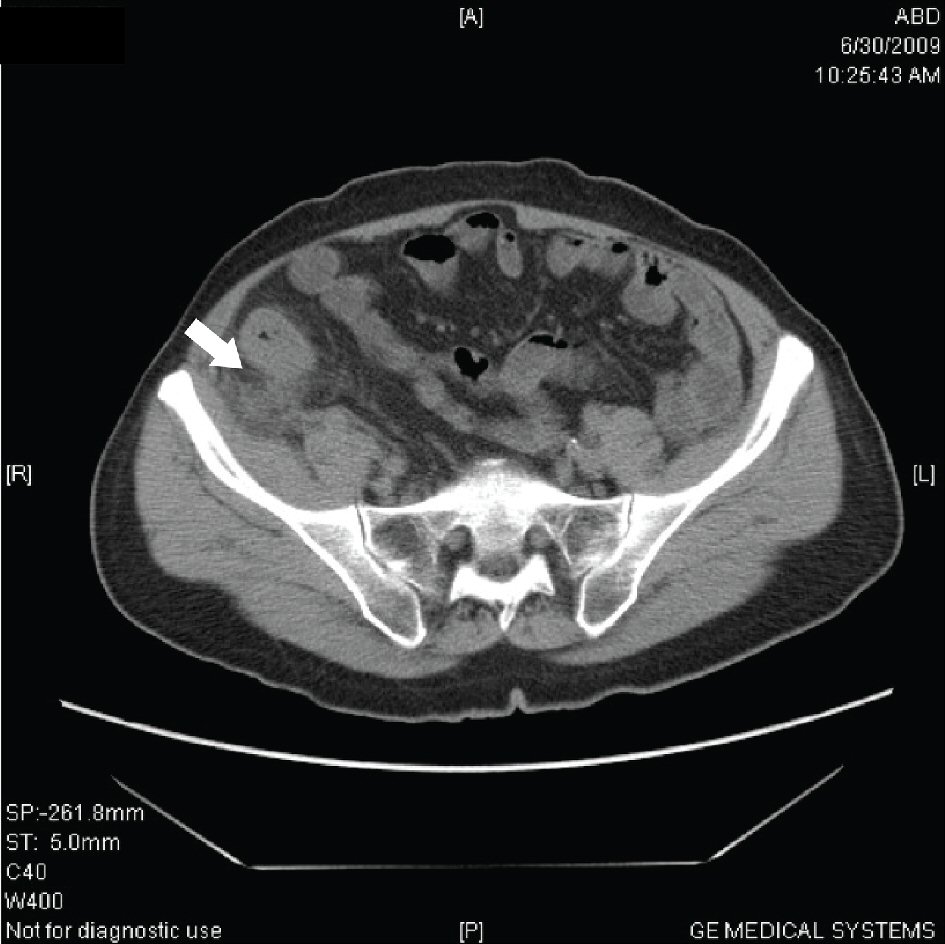

The outer to outer diameter of appendix on FACT scan of greater than 6 mm was demonstrated in 30 patients (31.6%). An intra-operative inflamed thickened appendix wall was seen in 87 patients (91.6%) (Fig. 3).

![]() Click for large image | Figure 3. Axial FACT scan at level of cecum shows a thickened, tubular structure arising from cecum; this is the inflamed appendix (arrowhead). Inflammation in this region has caused marked stranding of the pericecal fat (arrow). |